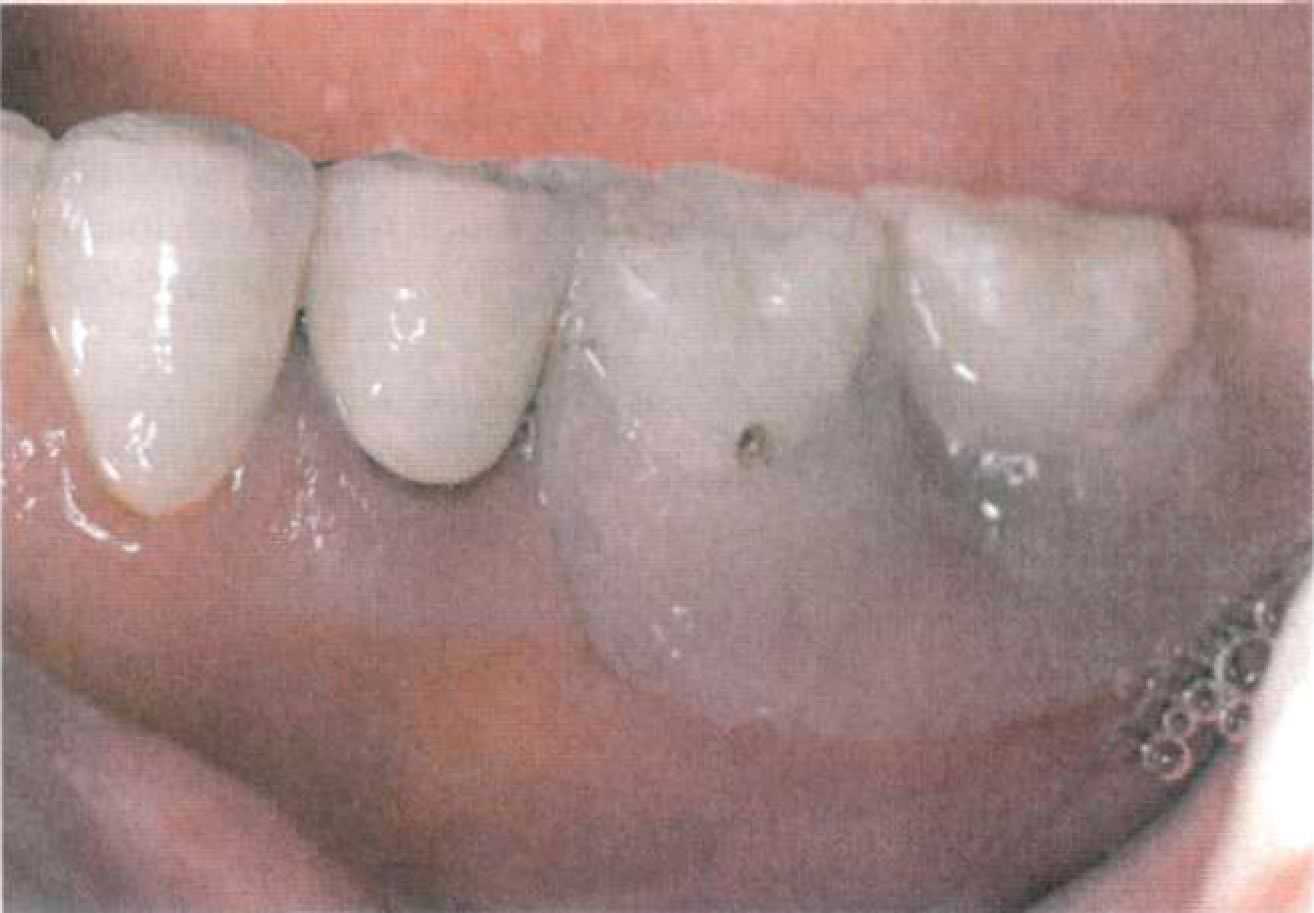

Этап 8. На заключительном этапе проводится проверка готового протеза в полости рта (рис. 116). Оценивают точность посадки аттачмена, проводят коррекцию окклюзионных контактов. Проверяют функции аттачмена (изначально он не должен быть активирован). Цементирование несъемной конструкции осуществляют под контролем надетой съемной части. Между патрицей и матрицей должен быть помещен вазелин для предотвращения попадания цемента.